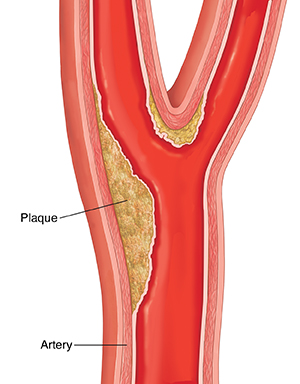

Clots form

When blood pressure is too high, it can damage blood vessel walls and create scar tissue. Fat and cholesterol (plaque) collect in the damaged spots. Blood cells stick to the plaque, forming a mass called a clot. A clot can block blood flow in the vessel.